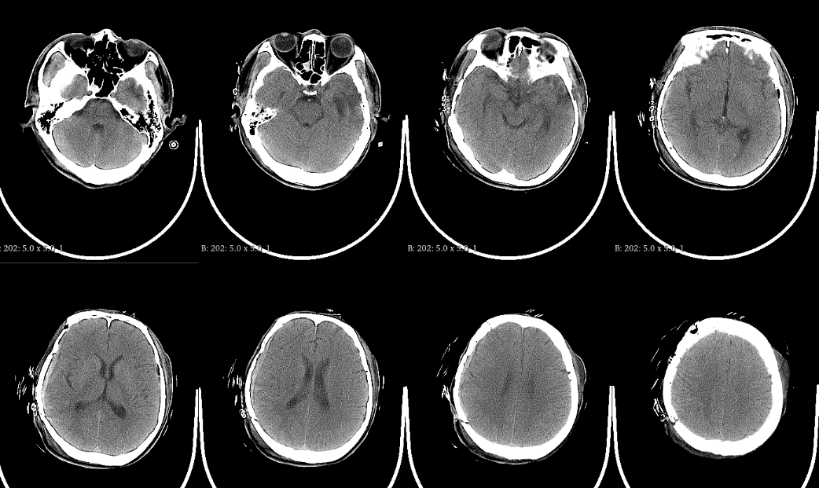

病例2:自体颅骨修补术前,去骨瓣术后3个月CT: